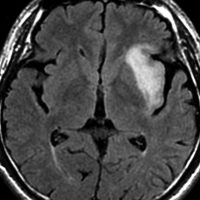

テモゾロマイド単独化学療法の例

2010年無症状の時の画像です。こんなのを手術で摘出したら認知機能が落ちて人格が変わります。だから経過観察しました。

2015年のテモゾロマイドを開始する前の画像です。2014年にちょびっと生検術をして1p/19q欠失,IDH変異はわかっていました。2015年に全般発作を起こしたので治療を開始しました。テモゾロマイドを 2年 24コース続けました。乏突起膠腫は大きくなる時,てんかんを生じることが多いです。

2020年の画像です。腫瘍はかなり小さくなって再燃(再発)していません。てんかんも抑制されて発作はありません。無症状です。

この例は,手術も放射線治療もしないで,乏突起膠腫が10年以上,制御できることを示しています。また,テモゾロマイド治療でてんかん発作が少なくなることも有名な事実です。

でも,現実はこんなに甘くない?  2025年時点で,治癒を目指すなら低線量放射線治療を加えるべきと考えられています。